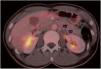

During follow-up, a possible para-aortic tumour recurrence and a lymphadenopathy suspected of malignancy were observed (Fig. 1). A PET-CT scan demonstrated a doubtful uptake in the retroperitoneal lesion (Fig. 2). In view of a possible tumour recurrence, the patient was assessed in conjunction with Internal Medicine. She had three major criteria for tuberous sclerosis (acoustic neurinoma, pulmonary lymphangioleiomyomatosis and retroperitoenal PEComa) and it was decided to start treatment with m-TOR inhibitors (sirolimus 2mg daily). Sirolimus levels are monitored every two months. After 3 months, a follow-up CT scan showed radiological improvement of the lesions with a decrease in the size of the mediastinal and retroperitoneal adenopathies described. (Fig. 3). At the present time, the patient has no signs of recurrence in control imaging tests and continues treatment with sirolimus, very well tolerated and without relevant adverse effects.